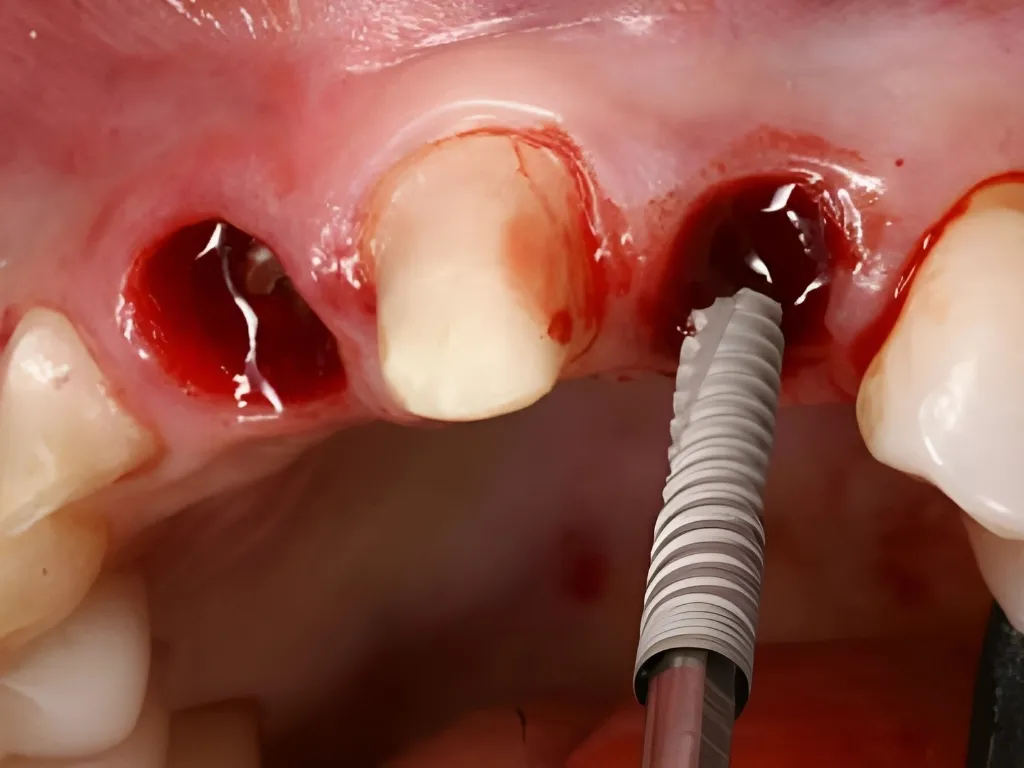

Diş Çekimi Sonrası Immediate Yükleme

Dr. Alejandro Freer

vaka_img